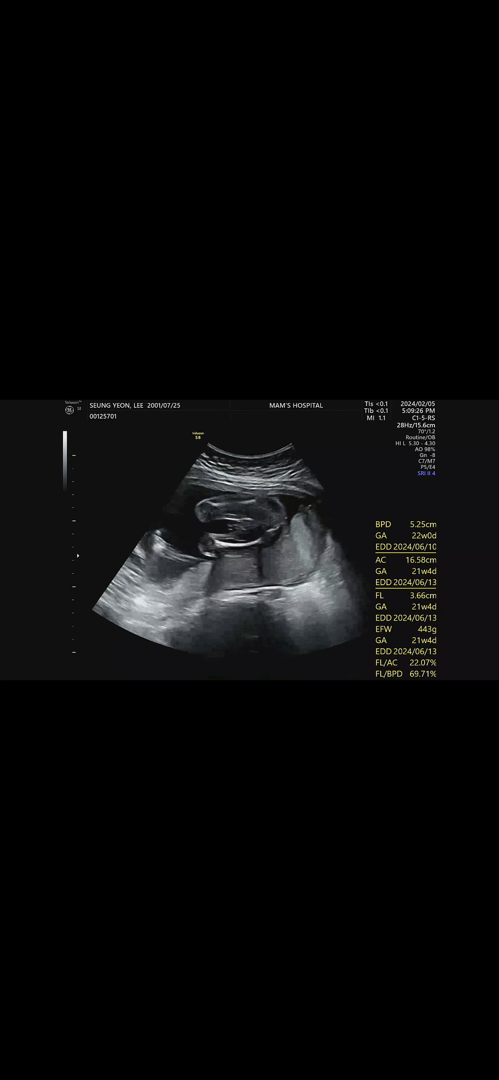

아들이 맞는거 같아요

20주 아기 성별봐주세용

의사선생님은 아들같다 하시는데 성별 반전은 없겠죠?!

반전없는 남아같아요😆

반전은 없을 것 같아요^^